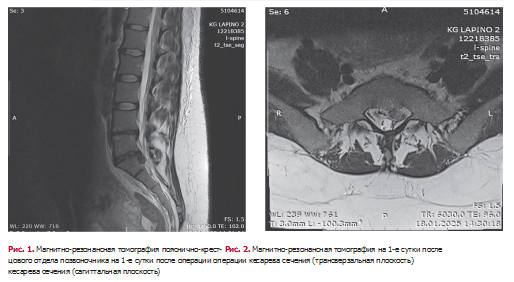

В 1-е сутки послеоперационного периода выполнено МРТ пояснично-крестцового отдела позвоночника: МР-признаки остеохондроза, спондилеза, спондилоартроза поясничного отдела позвоночника. Грыжа межпозвонкового диска LM-SI c его секвестрацией и компрессией корешка SI. Диффузное пролабирование дисков LIV-LV, LV-SI. Реактивные изменения по типу Modic 1 на уровне LIV-LV (рис. 1, 2).

Учитывая клиническую картину выраженного болевого монорадикулярного синдрома, двигательные расстройства в виде грубого пареза левой стопы, данные МРТ поясничнокрестцового отдела позвоночника (верифицированную секвестрированную межпозвонковую грыжу межпозвонкового диска на уровне LV-SI позвонков с компрессией SI корешка слева), пациентке показано оперативное лечение в объеме микрохирургического удаления грыжи межпозвонкового диска на уровне LV-SI позвонков в экстренном порядке.